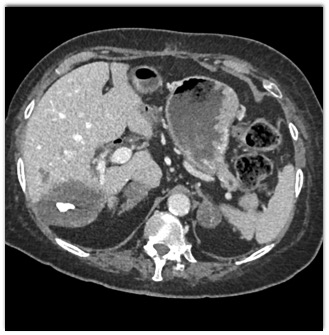

The best diagnosis in this patient with no known malignancy is?

hepatoma

metastatic colon cancer

sclerosed hemangioma

metastatic carcinoid tumor to the liver